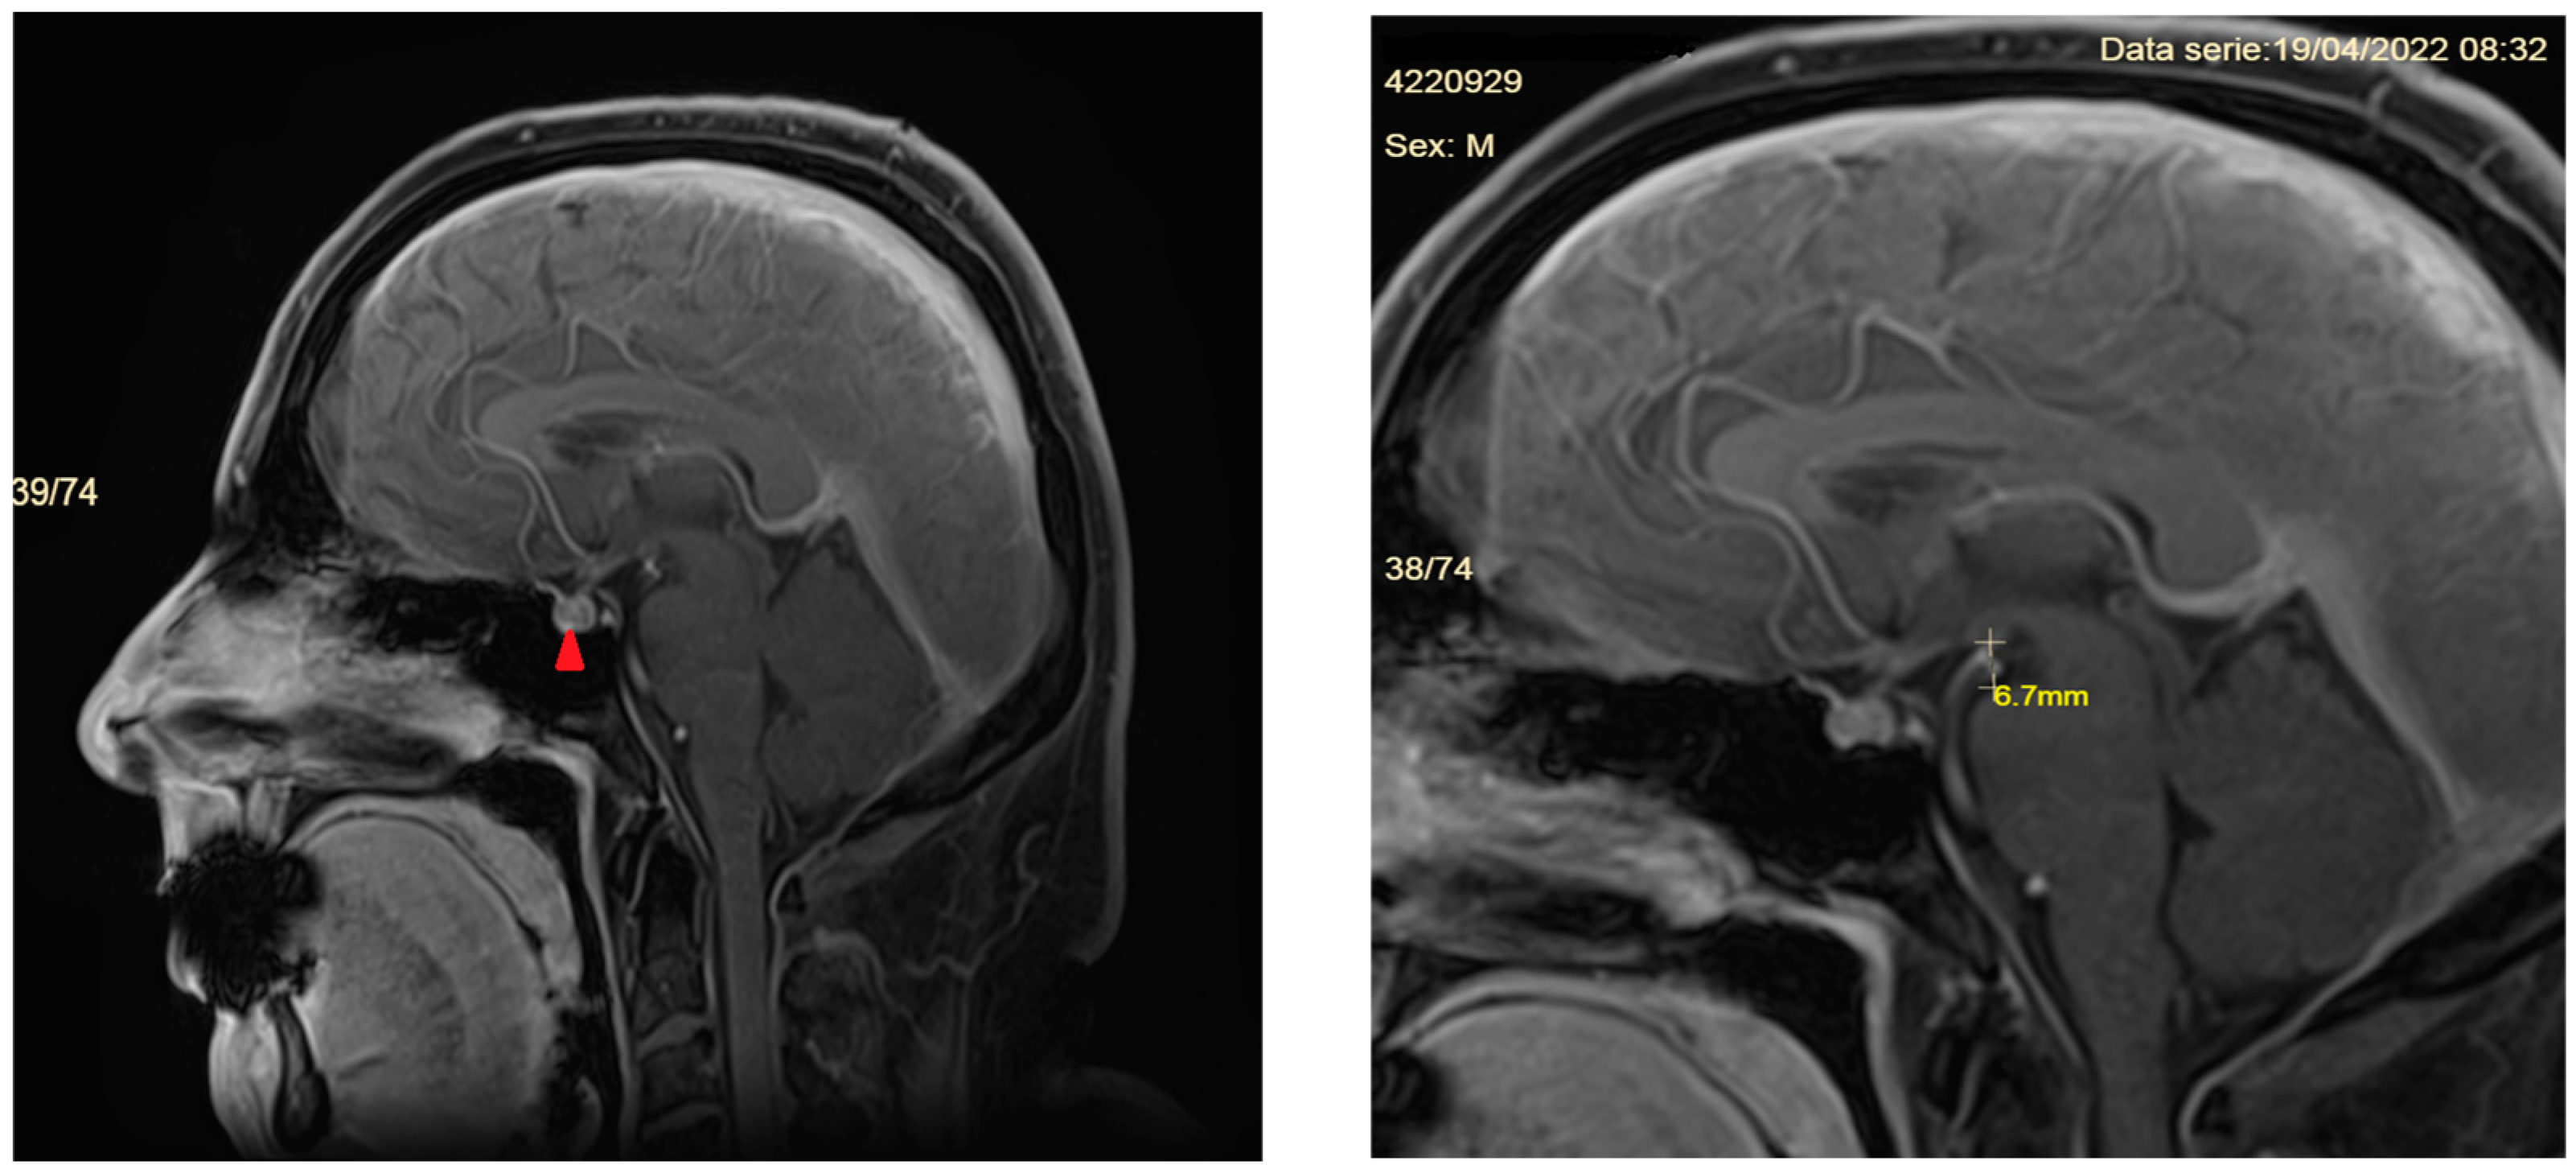

- Signs of brain sagging include flattening of the ventral pons, effacement of the prepontine and perichiasmatic cisterns, or downward displacement of the cerebellar tonsils and brain stem [5,8], which may mimic Chiari type 1 malformation. However, in SIH, the tonsils maintain normal shape and do not descend more than 5 mm below the foramen magnum [37]. Moreover, the findings associated with syringomyelia would argue for the diagnosis of Chiari type 1 malformation [32].

- Pituitary gland hyperemia leads to enlargement of the gland and can be mistaken for a pituitary adenoma [5].